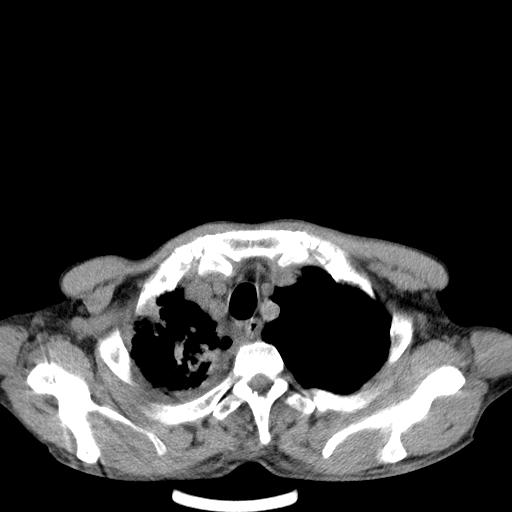

男性 75  咳嗽 一周前发热最高达39

右肺继发型tb并右侧tb性胸腔炎,右侧胸腔大量积液并右下肺膨胀不全,慢支肺气肿、多发肺大泡。建议抽胸水实验室检查并复查排除恶性在占位。

右上肺继发型肺结核,右胸腔中等量积液。

左上肺大泡。

结核的基础上有纵隔淋巴结肿大,右侧有胸水,但右侧纵隔反而窄,说明有肺有不张。

再就是右下肺有块影,和不张混合,还是不能除外肺癌。

补充材料,患者2月份ct片大致正常,双侧胸腔积液,2月份抽胸水未发现ca细胞,现患者发热,痰多,各气管通畅,

1)右肺继发型肺结核。2)左肺胸膜下多发性肺大泡。3)右侧胸腔积液。